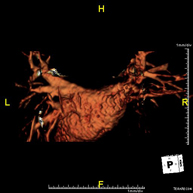

- Supra-aortic trunk MRI angiography

This non-invasive diagnostic procedure uses an electromagnetic field and radio waves (from a transmitter and receiver) to acquire high-definition anatomical images of the carotid and vertebral arteries in the neck. It is a radiation-free procedure. In most cases, paramagnetic contrast (gadolinium) is required. It enables non-invasive angiographic studies using a gadolinium injection, with subsequent 2D and 3D reconstruction using specialised workstations. Indicated for: cerebral circulatory problems, syncope.